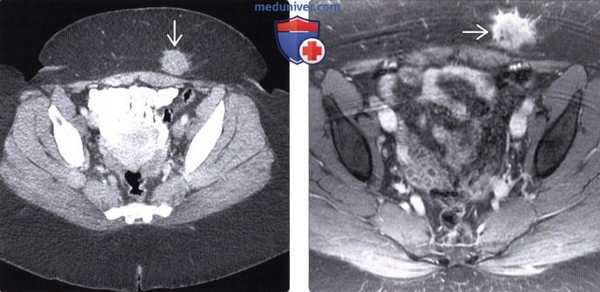

(Слева) На аксиальной КТ с контрастом визуализируются тонкая и ободочная кишка, выбухающие наружу сквозь травматический дефект в брюшной стенке. При операции в некоторых сегментах тонкой кишки были обнаружены разрывы серозной оболочки и ее повреждения отрывного характера, из-за чего потребовалось выполнение резекции.

(Справа) На аксиальной КТ с контрастным усилением определяется травматическая поясничная грыжа с выпадением внутрибрюшной жировой клетчатки, прикрытой только широчайшей мышцей спины. Также обратите внимание на инфильтрацию внутрибрюшной клетчатки возле грыжи. На операции был выявлен разрыв серозной оболочки нисходящей ободочной кишки. (Слева) На аксиальной КТ с контрастным усилением определяются петли тонкой кишки, не усиливающиеся при контрастировании, в большом количестве выбухающие сквозь травматический дефект в брюшной стенке с правой стороны. Определяются также признаки активного артериального кровотечения. Большая часть кишки была обнаружена нежизнеспособной при операции.

(Справа) На аксиальной КТ с контрастным усилением определяется разрыв мышц брюшной стенки в нижних отделах слева, кроме того, мышцы оторваны от места своего прикрепления к гребню подвздошной кости. Обратите внимание на наличие подкожной гематомы в прилежащих отделах. Это - типичный пример повреждений, возникающих при неправильно зафиксированном ремне безопасности.

(Справа) На аксиальной КТ с контрастным усилением определяется травматическая поясничная грыжа с выпадением внутрибрюшной жировой клетчатки, прикрытой только широчайшей мышцей спины. Также обратите внимание на инфильтрацию внутрибрюшной клетчатки возле грыжи. На операции был выявлен разрыв серозной оболочки нисходящей ободочной кишки.

(Слева) На аксиальной КТ с контрастным усилением определяются петли тонкой кишки, не усиливающиеся при контрастировании, в большом количестве выбухающие сквозь травматический дефект в брюшной стенке с правой стороны. Определяются также признаки активного артериального кровотечения. Большая часть кишки была обнаружена нежизнеспособной при операции.